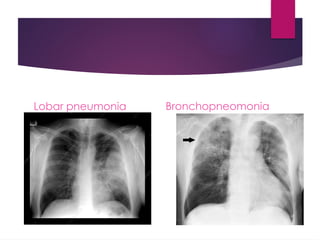

Anatomical classification

Lobar pneumonia Bronchopneomonia

Interstitial pneumonia